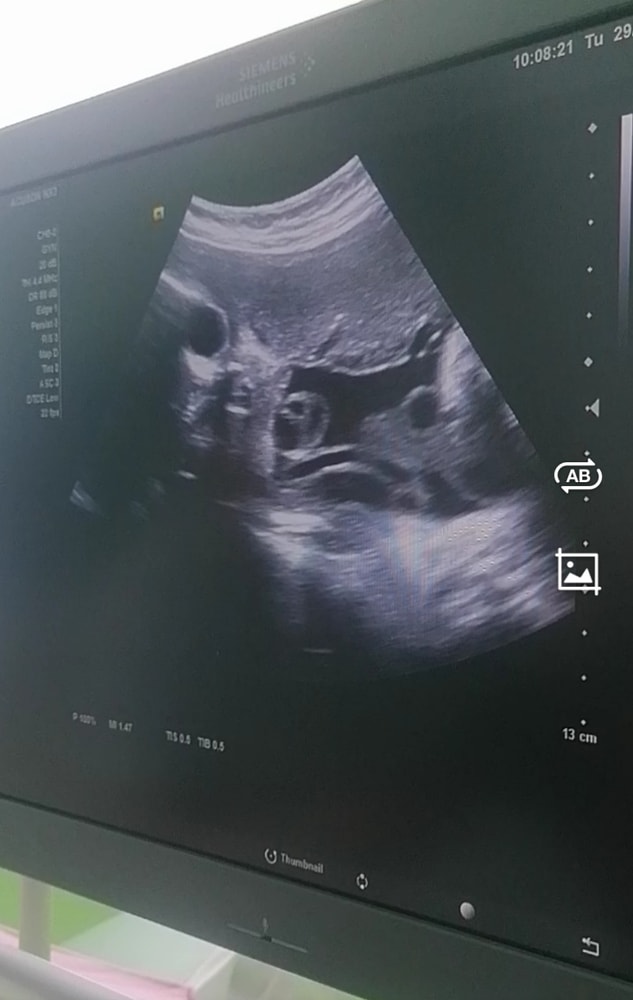

Узи в 32 недели.

УЗИ, КТГ, доплерПрошла сегодня узи платно, через 10 дней будет бесплатное от жк. Есть хорошее и плохое. Плохое это в плаценте обнаружили микрокальцинаты, врач спросила болела я вирусными заболеваниями, а я как раз сейчас болею, без температуры. Сказала что во время болезни вирусом очень страдает плацента, так как она защищает плод от вирусов, но поражение не сильное, так как воды чистые, количество вод норма, артерии тоже норма, беспокоится пока не нужно. Мистика творится с плацентой, в 13, 19, 32 недели она была по передней стенке, а в 21, 24 неделю по задней, такое разве возможно? Сама пуповина очень длинная, из-за этого дочь обматала её вокруг шеи, на мониторе как шарфик выглядела, и одновременно кусала или сосала её, так не смогли понять, но обвитие слава богу не тугое, но нужно часто делать ктг. У кого было так? Боюсь что из-за того что пуповина длинная, второй узел на шею не закинет🫣. Попросила посмотреть ещё раз пол чтоб точно быть увереной, но дочь и там успела обмотаться пуповиной🤦. Ноги были скрещены и между ног была пуповина, как на канате висит на ней. По органам всё хорошо, похожа на меня☺️, копия я, папа мимо проходил🫢. Из всех детей, только в четвёртый раз повезло с моей внешностью🥰. Степень зрелости плаценты 2, рассчитывала на 1, но из-за микрокальцинатов поставили 2 зрелость, сказали нельзя перенашивать. Вес малышки ровно 2кг. У кого такой вес был, с каким весом родили и на каком сроке? Срок по узи на 1 день отстаём, но врач сказала это норма.